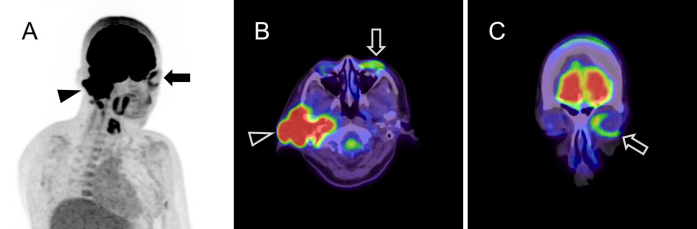

A Case of the Monocle Sign in Facial Nerve Palsy Caused by External Auditory Canal Cancer on 18F-fluorodeoxyglucose-positron Emission Tomography/Computed Tomography.